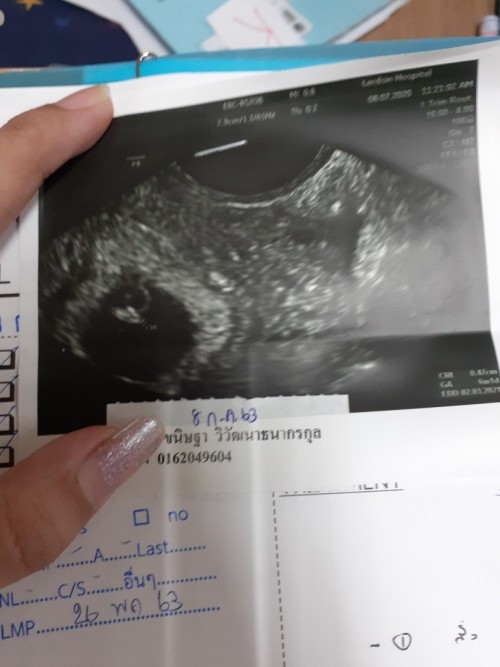

ซาวตอน5วีคไม่เจอเหมือนกันค่ะ เห็นแค่ถุงตั้งครรภ์ มาเจอน้อง พร้อมหัวใจตอน11วีค บำรุงร่างกายดีๆนะคะ ทานโฟลิค ทานอาหารครบ5หมู่ค่ะ

ตอน 6 สัปดาห์ซาวด์ทางหน้าท้องก็เห็นแค่ถุงเหมือนกันค่ะ แต่พอซาวด์ทางช่องคลอดเห็นน้องชัดเลย เห็นหัวใจเต้นด้วย

เจอแต่ถุงเหมือนกันค่ะ6วีค แต่พอ7วีคผ่านช่องคลอดก็เจอหัวใจเต้น เจอตัวแล้วค่ะ ใจเย็นๆนะค้า